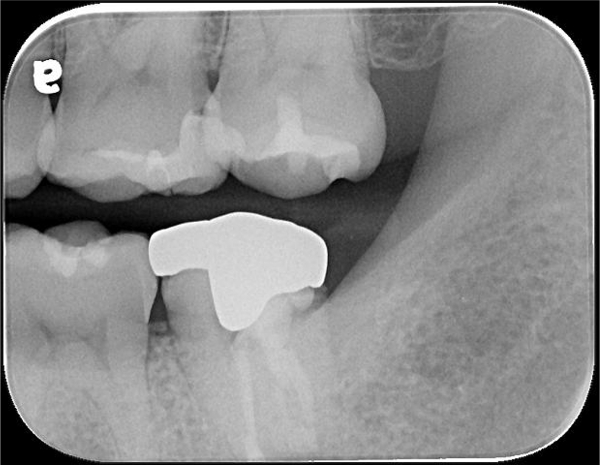

治療前,二次蛀牙

蛀牙未到牙髓

陶瓷崁體

陶瓷崁體邊緣完整